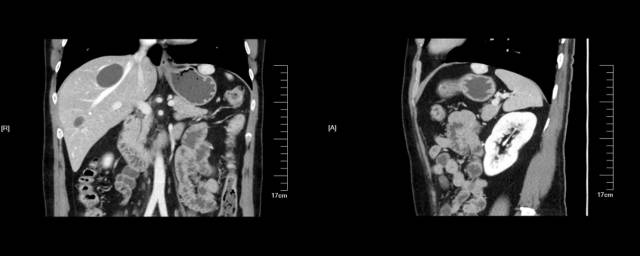

下面患者在外院胃镜和CT(图 A-B)均考虑胃底粘膜下肿瘤,拟双镜联合切除。

术前来我院完善超声内镜检查提示肝左叶近膈顶血管瘤(图A-B)

图A:环扫EUS提示肝脏近膈顶类圆形血管瘤(白色箭头);图B:线阵EUS见病灶上方的固有肌层完整(白色箭头)

EUS考虑血管瘤,动员患者在我院复查增强CT,常规水平成像可见胃底软组织影(下图 白色箭头)。

但经冠状位和矢状位重建放大后证实来源于肝左叶近膈顶部外生性血管瘤压迫胃底(下图A-B 黄色箭头处)。